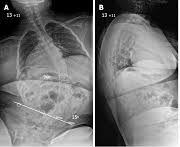

JBJS.2007から引用

デュシェンヌ型の側弯は前に書いた健常者の特発性側弯とはかなり異なるものです。

通常の側弯は骨自体が曲がってくるのですが、デュシェンヌ型の側弯は周りの筋肉が低下して背骨がまっすぐ保てなくなります。

通常の側弯は骨の変形で硬めに対して、デュシェンヌ型の側弯は柔らかくて寝ているときよりも座ると体重を支えられなくなり非常に曲がります。